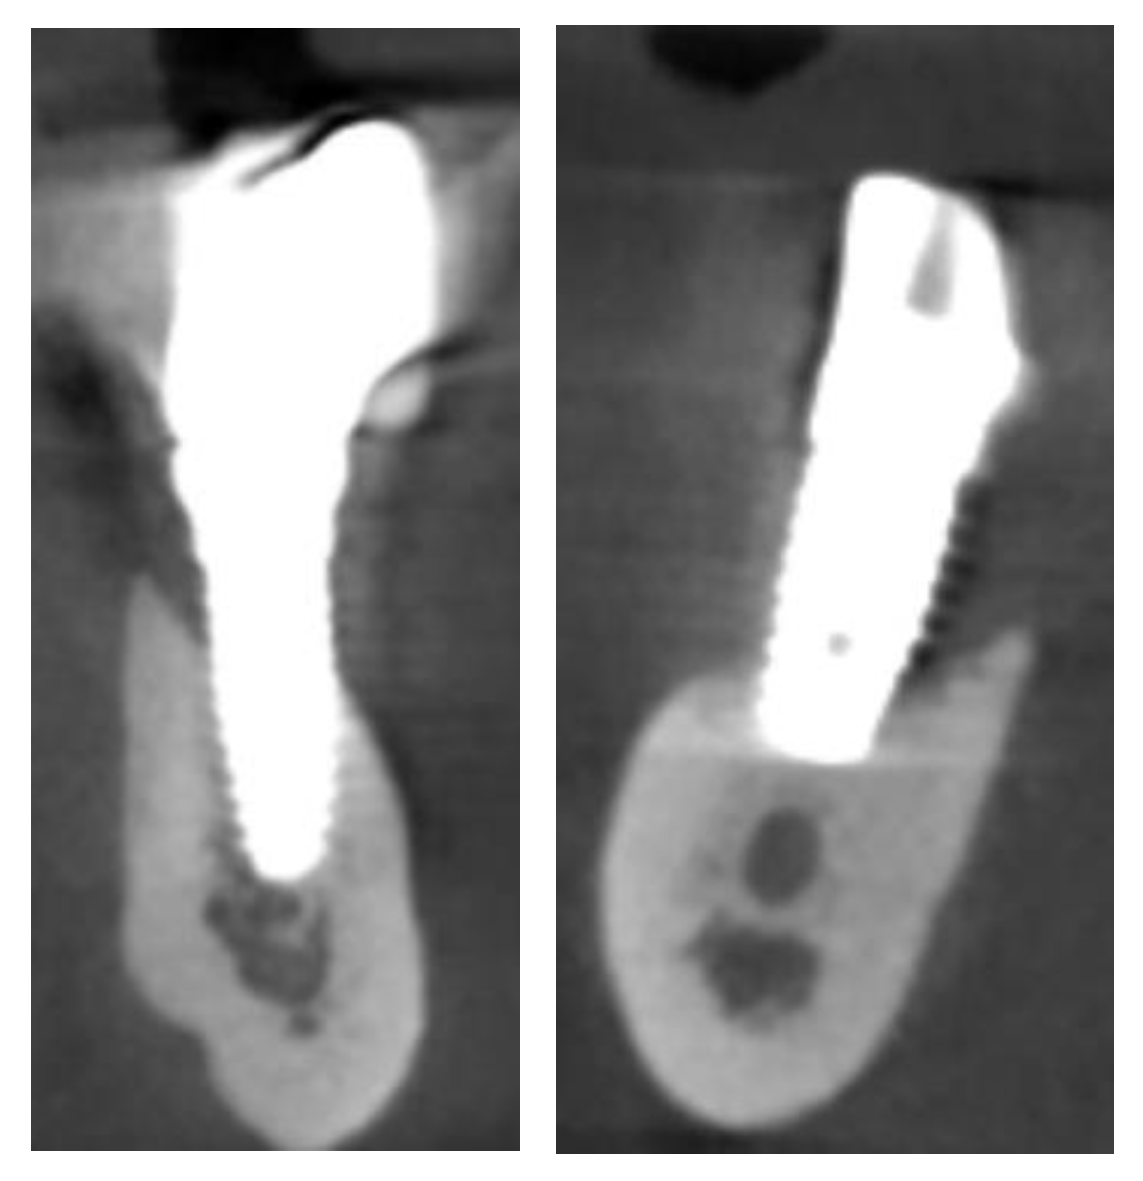

2. Materials and Methods

2.1. Planning

2.4. Surgery